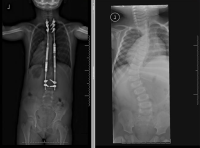

Infantile Idiopathic Scoliosis: Angela's Story

From twelve months to three years old Angela underwent multiple procedures where she went under anesthesia to get a close to full body cast molded to her body, to help fight against the ever-moving curve. At only three and a half years old she had her first spinal surgery. In the last year, she had three more surgeries. "It never gets easier to watch your child go in for surgery. However, I never doubted for a moment that she was in the best possible hands. When we first met Dr. Vitale I was scared that my daughter would never walk normally. Now today I watch her run and play with her friends and just looking at her you would never know that she had any kind of medical problems. I know for a fact that none of this would be possible without Dr. Vitale. There is no other doctor that I would trust with my daughter."